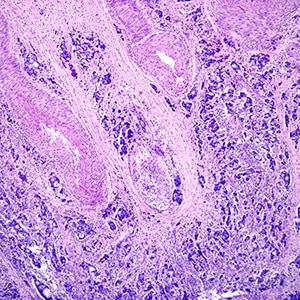

Some cancer cells look like normal, noncancerous cells—these tend to be less aggressive than cancer cells that look very different from normal cells. For most cancer types, the tumor is assigned a grade, with grade 1 tumors looking the most normal and grade 5 tumors the most abnormal.

The Gleason score accounts for these features by combining grades from different regions of the prostate cancer. To calculate the score, pathologists analyze prostate tissue collected from a biopsy, identify the two most representative cellular patterns, and assign each of these a grade.

The grades are then added together, and the sum is the Gleason score.

When reporting this score, pathologists typically include the grade of each pattern, with the grade of most representative pattern listed first. For example, if a cancer’s most common pattern were grade 4 and the second most common were grade 3, then the report may say “Gleason score 7 (4 + 3)” or “Gleason score 4 + 3 = 7.” Since each cellular pattern can have a grade between 1 and 5, Gleason scores can theoretically range from 2 (1 + 1) to 10 (5 + 5), but most prostate cancers have scores of 6 or higher.